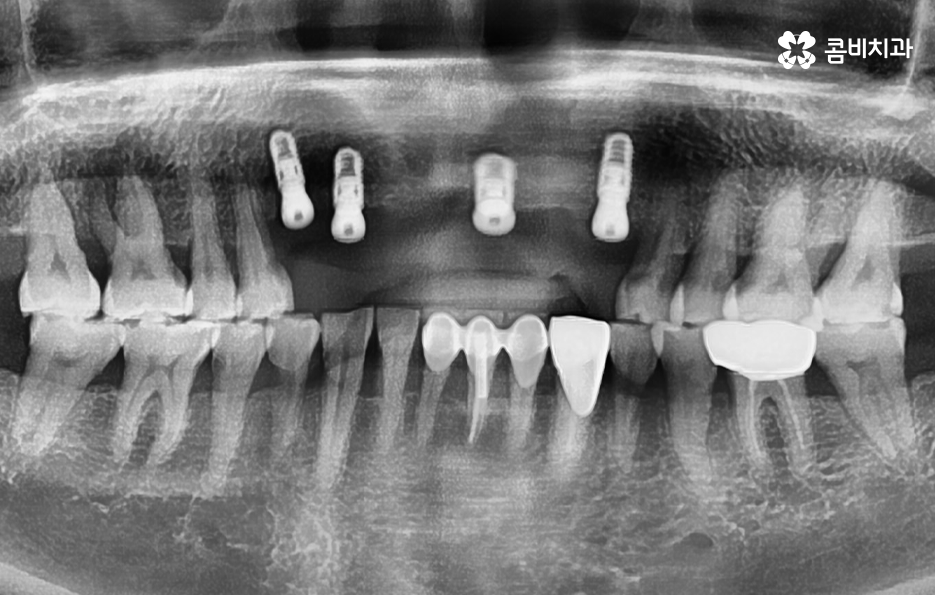

오늘 포스팅의 사례의 경우 앞니를 이미 잃은 상태였지만 주변 치아를 활용하여 브릿지로 연결해놓은 상태에서 기존의 치아가 버티지 못하여 앞니임플란트 하게 된 경우라고 볼 수 있는데요.

임플란트 치료는 되도록 치아를 상실한 개수와 1:1로 비례하여 식립하는 것을 권장하고 있는데 그 이유는 치아의 저작력에 있어서 우리의 모든 치아를 각각의 역할과 기능이 있고 압력에 대한 분산 효과도 있는데요

따라서 앞니임플란트를 해야하는 경우에는 치아를 잃게 될 경우 곧 바로 치료를 하는 것이 중요하며 임플란트의 수명과 심미성을 위해서도 치아를 잃은 개수만큼 치료하는 것을 권장하고 있는데요.

일반적으로 앞니의 주된 상실 요인은 젊은 분들의 경우 사고나 충치로 인한 경우가 많지만 중년 이후에는 치주질환으로 인해 잇몸이 약해져서 치아를 상실하는 풍치로 인한 경우가 많을 거예요.

잇몸 상태와 전신 건강이 양호한 경우에는 원데이임플란트를 통해 앞니임플란트 치료를 많이 진행하지만 오늘 케이스처럼 이미 치아를 발치한 후 시간이 지난 경우나 치주염으로 인해 잇몸 뼈가 녹고 염증이 심한 경우에는 빠른 치료보다는 잇몸을 충분히 회복하여 건강하고 안전한 결과에 더 초점을 두고 있는데요.